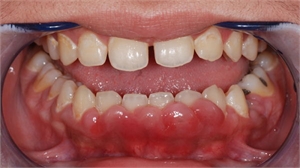

Enlargement of gums or gingiva is called gingival hyperplasia in the dental terms. This condition occurs due to abnormal multiplication of gingival tissue cells caused by various factors. Typical findings for gingival hyperplasia are swollen and enlarged gums. If you are suffering from gingivitis there will be gum bleeding as well as tenderness. The teeth get covered with the gums if the infection is too intense.  The patient is examined by a dentist and then the patient is sent for further examination if any further complications are seen.